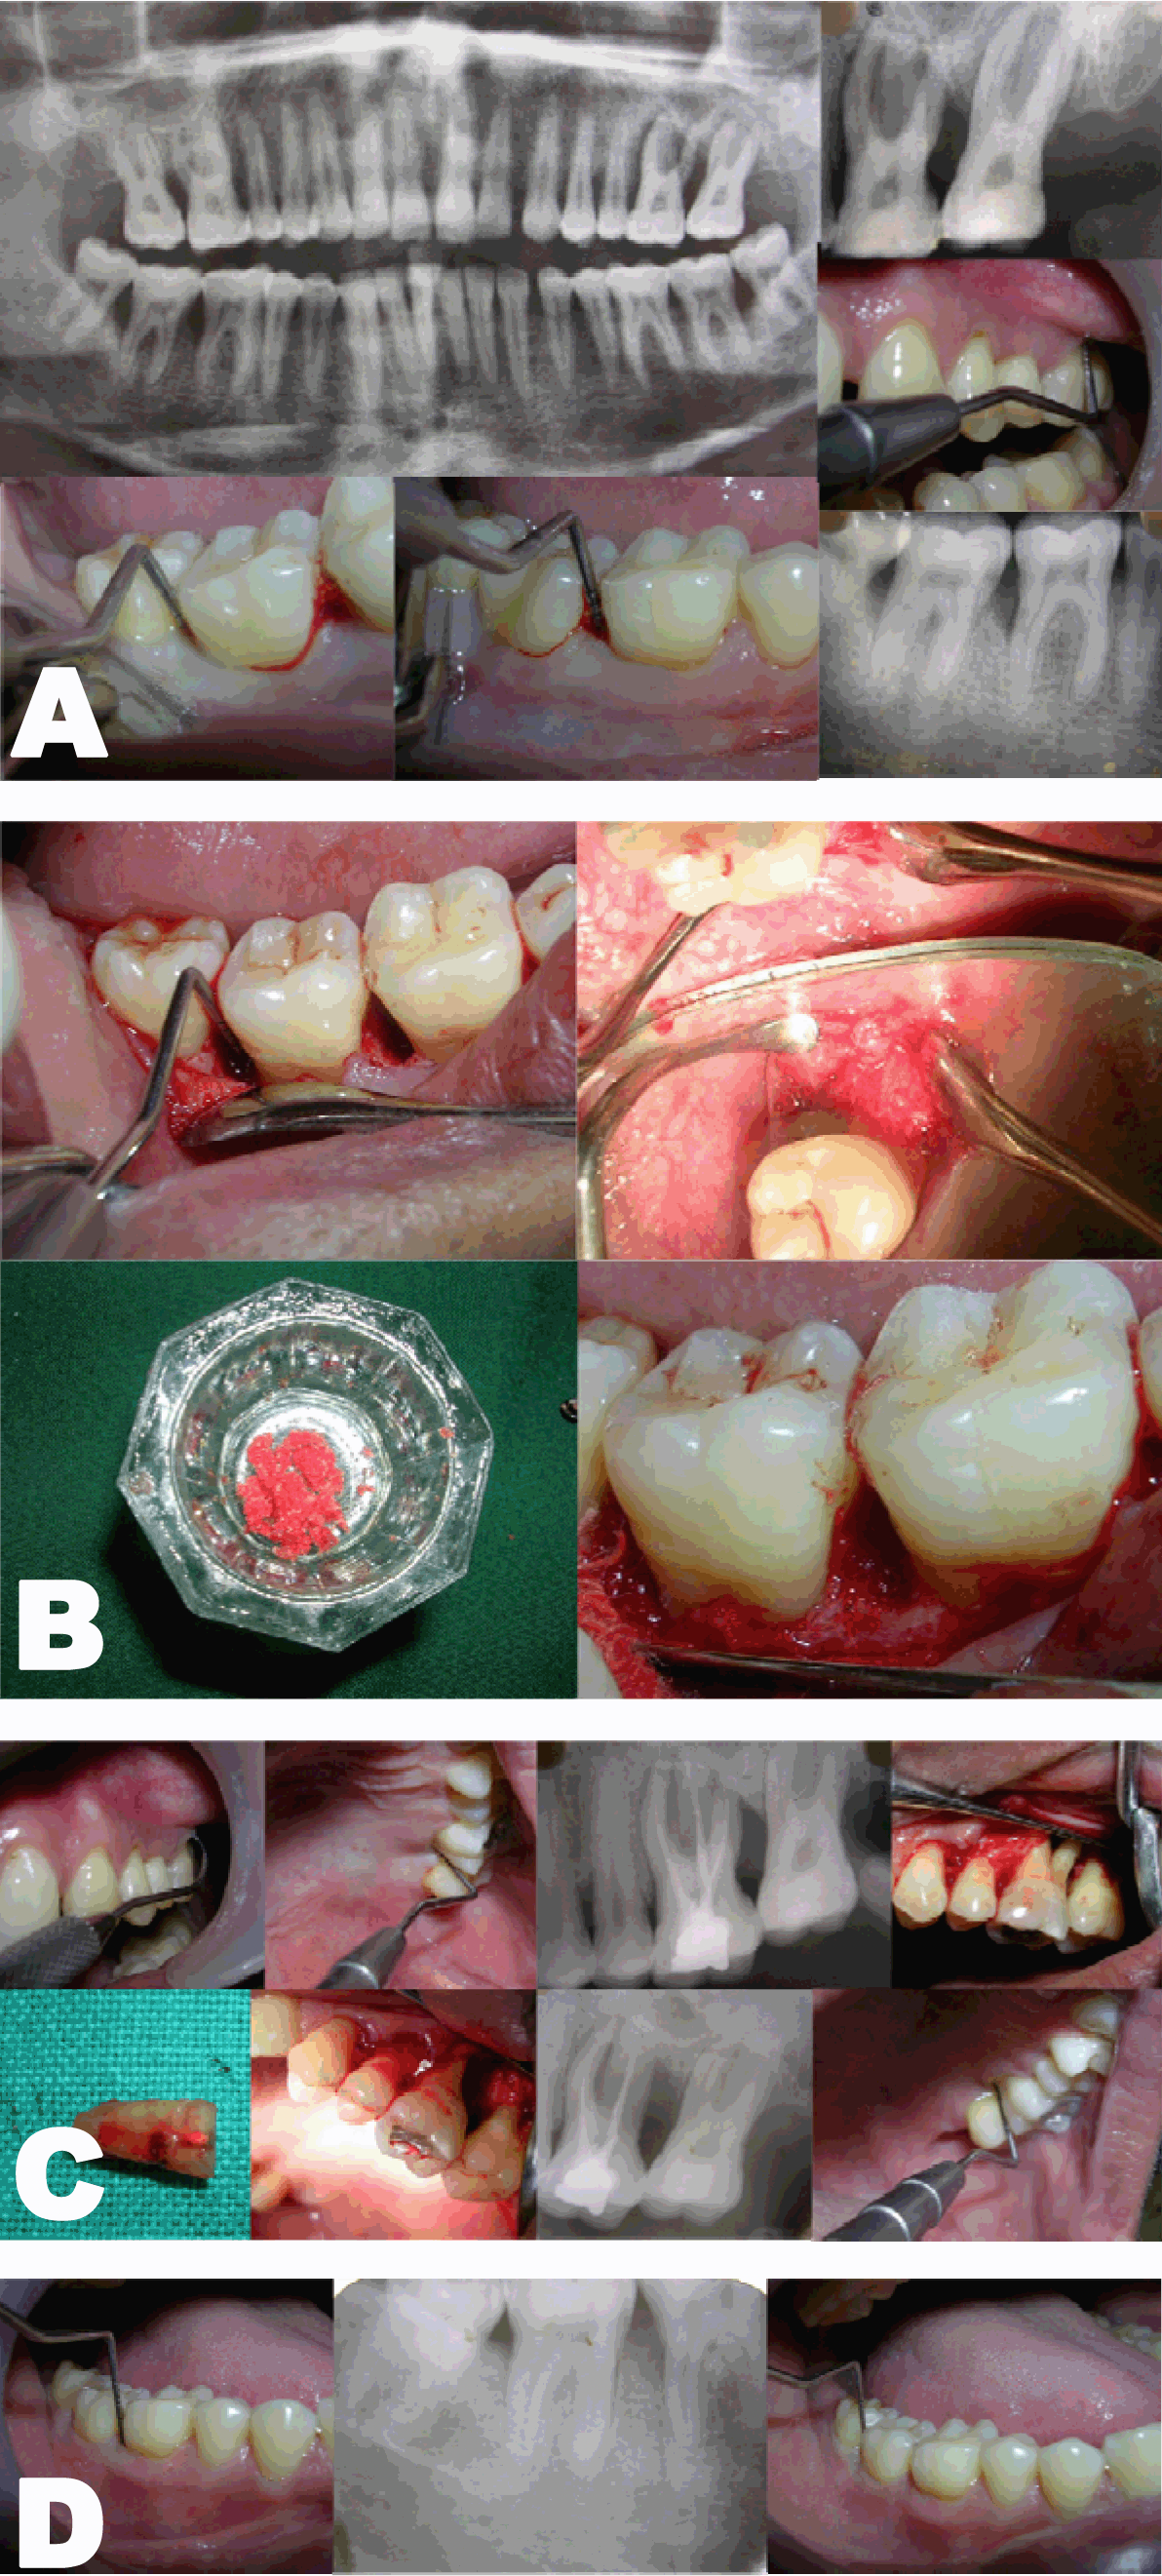

Case 1: A 36-year-old male reported with the chief complaint of pain and bleeding from gums since three months. He also complained of pus discharge from maxillary left last molar since one month. On clinical examination, there were deep pockets > 5 mm in 46, 36 and 27. There was bleeding on probing in all the three teeth involved. The tooth #27 also had Grade II mobility with purulent discharge from the pocket on probing. An orthopantomogram (OPG) revealed infrabony defects on distal aspect of 46 and 36. The tooth #27 had a large periapical radiolucency surrounding the root (Figure 1A). Based on history, clinical findings and radiographic evaluation a diagnosis of Localised Aggressive Periodontitis with an endo-perio lesion in 27 was arrived at.

After phase I therapy and endodontic treatment 27, three different procedures were planned to correct the osseous defects. The first surgery was carried out in 36 region. After debridement, bone graft substitute mixed with platelet-rich plasma (PRP) was placed inside the defect (Figure 1B). In the second surgery involving 46, a bone graft substitute was placed which was covered with a resorbable membrane (Figure 1C). In 27, a complete debridement was carried out.

Figure 1: (A) Preoperative, orthopantomogram and clinical evaluation, (B) Tooth #36 treated with platelet-rich plasma bone graft substitute. (C) Tooth # 46 treated using resorbable membrane with bone graft substitute. (D) Postoperative clinical and radiographic evaluation (Case 1).

Case 2: A 29-year-old male reported with the chief complaint of pain and bleeding in relation to upper left tooth since one month. He also complained of dull pain in lower left tooth since three months. Clinically, there were deep periodontal pockets on both mesial and distal aspects of 25 and mesial aspect of 35. Radiographic picture showed osseous defects on mesial and distal aspects of 25 and on mesial aspect of 35 (Figure 2A). A diagnosis of localized aggressive periodontitis was made taking into consideration his positive family history, clinical evaluation and X-rays. After completing phase therapy, surgeries were planned for 25 and 35 using a bone graft substitute in combination with a resorbable membrane (Figure 2B-C).

Figure 2: (A) Preoperative clinical evaluation and radiographs. (B) Tooth #25 treated using bone graft substitute with resorbable membrane. (C) Tooth #35 treated using bone graft substitute with resorbabale membrane. (D) Postoperative clincial and radiographic evaluation (Case 2).

Case 3: A 34-year-old male reported with the chief complaint of pain, bleeding and pus discharge in relation to upper left tooth since two months. He also complained of bleeding from gums in lower posteriors since one year. Clinically, there was bleeding and pus discharge on probing from 26 region. There was a deep periodontal pocket and Grade III furcation involvement. There were pockets > 6 mm on distal aspect of 46, 47 and 36 regions. An OPG revealed infrabony defects on distal aspect of 46, 47 and 36. There was a large radiolucency around the roots of 26 and severe bone loss especially around the distobuccal root of 26 (Figure 3A). After phase I therapy and endodontic treatment in 26, root resective surgery was planned. The distobuccal root was resected out since there was complete absence of bone around it. After thorough debridement, a bone graft substitute was placed and flap sutured (Figure 3B). Further surgeries were planned to eliminate the osseous defects in 46, 47 and 36 regions. In 36, 46 area, the plan was to use autogenous bone chips from maxillary tuberosity mixed with bone graft substitute making a composite graft. After debridement, the defects were filled with this composite graft (Figure 3C). In 36 region, a debridement followed by placement of bone graft substitute was carried out.

Figure 3: (A) Preoperative clinical evaluation and OPG. (B) Tooth #46, 47 treated using autogenous graft. (C) Tooth #26 treated using root resective surgery. (D) Tooth #46, 47 Postoperative radiographic evaluation (Case 3).

In the Case 1, clinical as well as radiographic picture at sixth month showed reduction in pocket depth and osseous lesions in 36, 46 and 27 (Figure 1). In Case 2, at the time of evaluation at ninth month postoperative, there was significant decrease in the radiolucency in 25, 35 as well as reduction in the pocket depth (Figure 2). In Case 3, following root resection, 26 was clinically healthy and a radiograph at sixth month revealed reduction in radiolucency around the roots (Figure 3D). In Case 4 involving tooth #31, the tooth appeared healthy with no pain or pus discharge. Radiograph showed some amount of bone fill.